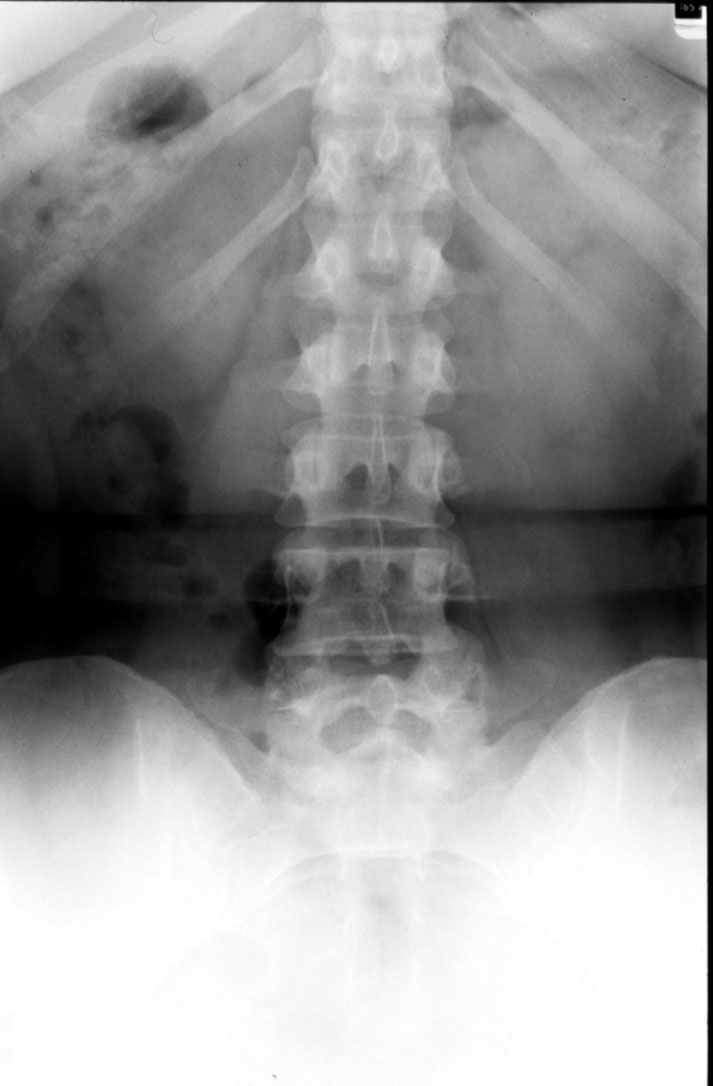

Normal Lumbar Spine (AP) -- Identify: vertebral body, pedicle, lamina,

spinous process, transverse process, intervertebral disc